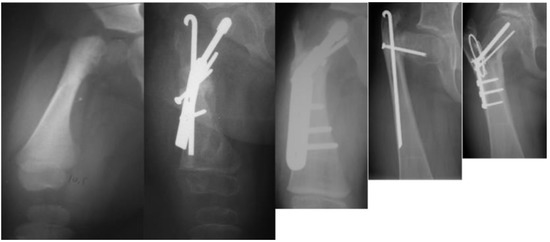

The occurrence of recurrent coxa vara and persistent delayed ossification were specifically analyzed (Figure 5). Statistical analysis was performed using Fisher’s exact test to compare the outcomes of the different treatment groups. All results are reported according to the two-tail p-value calculation.

Figure 5. Radiographs showing: preoperative type 1b CFD (leftmost); after SUPERhip procedure fixed with infant sliding hip screw (second to left); the neck did not ossify so the infant sliding hip screw was changed to a larger size sliding hip screw (revision SH) a year later (middle); delayed ossification of the neck persisted and two years later the hip screw was removed and recurrent varus deformity occurred (second to right); a second revision SH was performed with blade plate fixation and insertion of BMP2 and the neck fully ossified (rightmost).